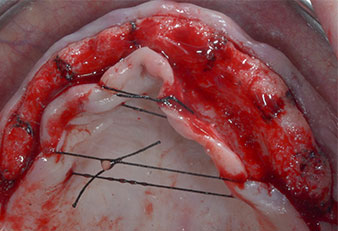

Abb. 1: Präoperative Ansicht des Kieferkamms, die Implantatpositionen wurden mithilfe einer Kunststoff-Bohrschablone markiert. Wegen des niedrigen Kieferkamms sind im Seitenzahnbereich sehr kurze Implantate geplant.

Abb. 2: Nach dem Kieferkammschnitt und der Präparation der Mukoperiostlappen werden die Implantatpositionen auf den Knochen übertragen.

Wegen des relativ harten Knochens (D2) an den Positionen 11 und 21 wurden die 10 mm langen Implantatlager in diesem Bereich abschließend mit einem 4-mm-Spiralbohrer, dem chirurgischen Winkelstück WS-75 L von W&H und dem W&H Implantmed Implantologiemotor in Verbindung mit dem optionalen W&H Osstell ISQ module präpariert. Im Gegensatz dazu wurde der weiche Knochen der Implantatlager im Seitenzahnbereich mit dem Piezomed I3P auf den abschließenden Durchmesser von 3 mm erweitert. Die Implantate wurden dann transgingival eingesetzt, die Einheildauer betrug drei Monate (Abb. 6-10). Die vorhandene Prothese wurde auf vier provisorischen Implantaten abgestützt (Abb. 8).

10-mm-Tissue-Level-Implantat

Abb. 6: Ein 10-mm-Tissue-Level-Implantat wird an Position 21 platziert. Das Implantat an Position 11 und die drei linken posterioren 4-mm-Implantate wurden bereits eingesetzt.